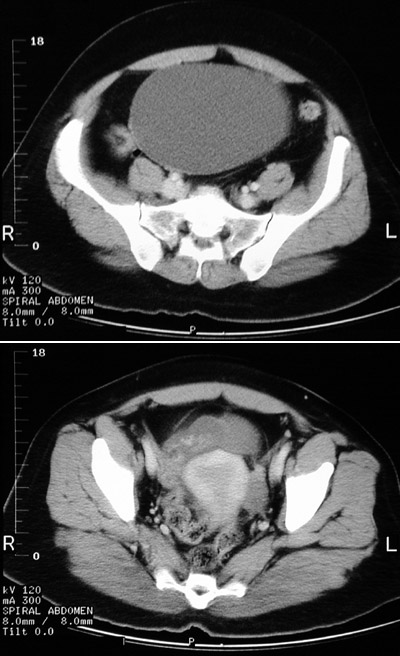

![]() | A large cystic mass is seen filling much of the pelvis in the upper panel of this pelvic CT scan. The unilocular mass has a thin wall and is fluid-filled. The inferior margin of the mass can be seen to attach to the right ovary next to the bladder, where the wall is somewhat thickened and irregular. This is a benign ovarian cystadenoma. |